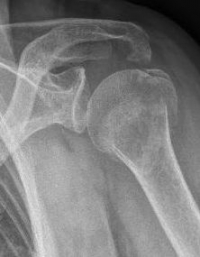

The first indication of a proximal humeral fracture is provided by the accident. Typical is a fall on the shoulder or the arm, also as indirect trauma with fall on the outstretched hand or the elbow. Furthermore, a physical examination is indispensable for the diagnosis of the above symptoms. The shoulder should be x-rayed in 3 planes. Sometimes, a supplementary computer tomography is necessary for further diagnosis and exact determination of the course of the fracture. Magnetic resonance imaging is only performed if there is a suspicion of a dislocation of the shoulder joint or a malignant underlying disease as the cause of the fracture.

There are many different classifications for the codification of proximal humeral fractures. A frequently used classification is NEER. Depending on the displacement, tilting and exact localization of the fracture clefts, the classification is divided into a total of 6 classes (NEER I - VI).

Picture: The subcapital humeral fracture shown here in the axis is not broken and only slightly bruised, so that a conservative therapy is possible. The left image shows the follow-up after 3 weeks. The patient has already started physiotherapy. The x-ray shows an increase bone healing.